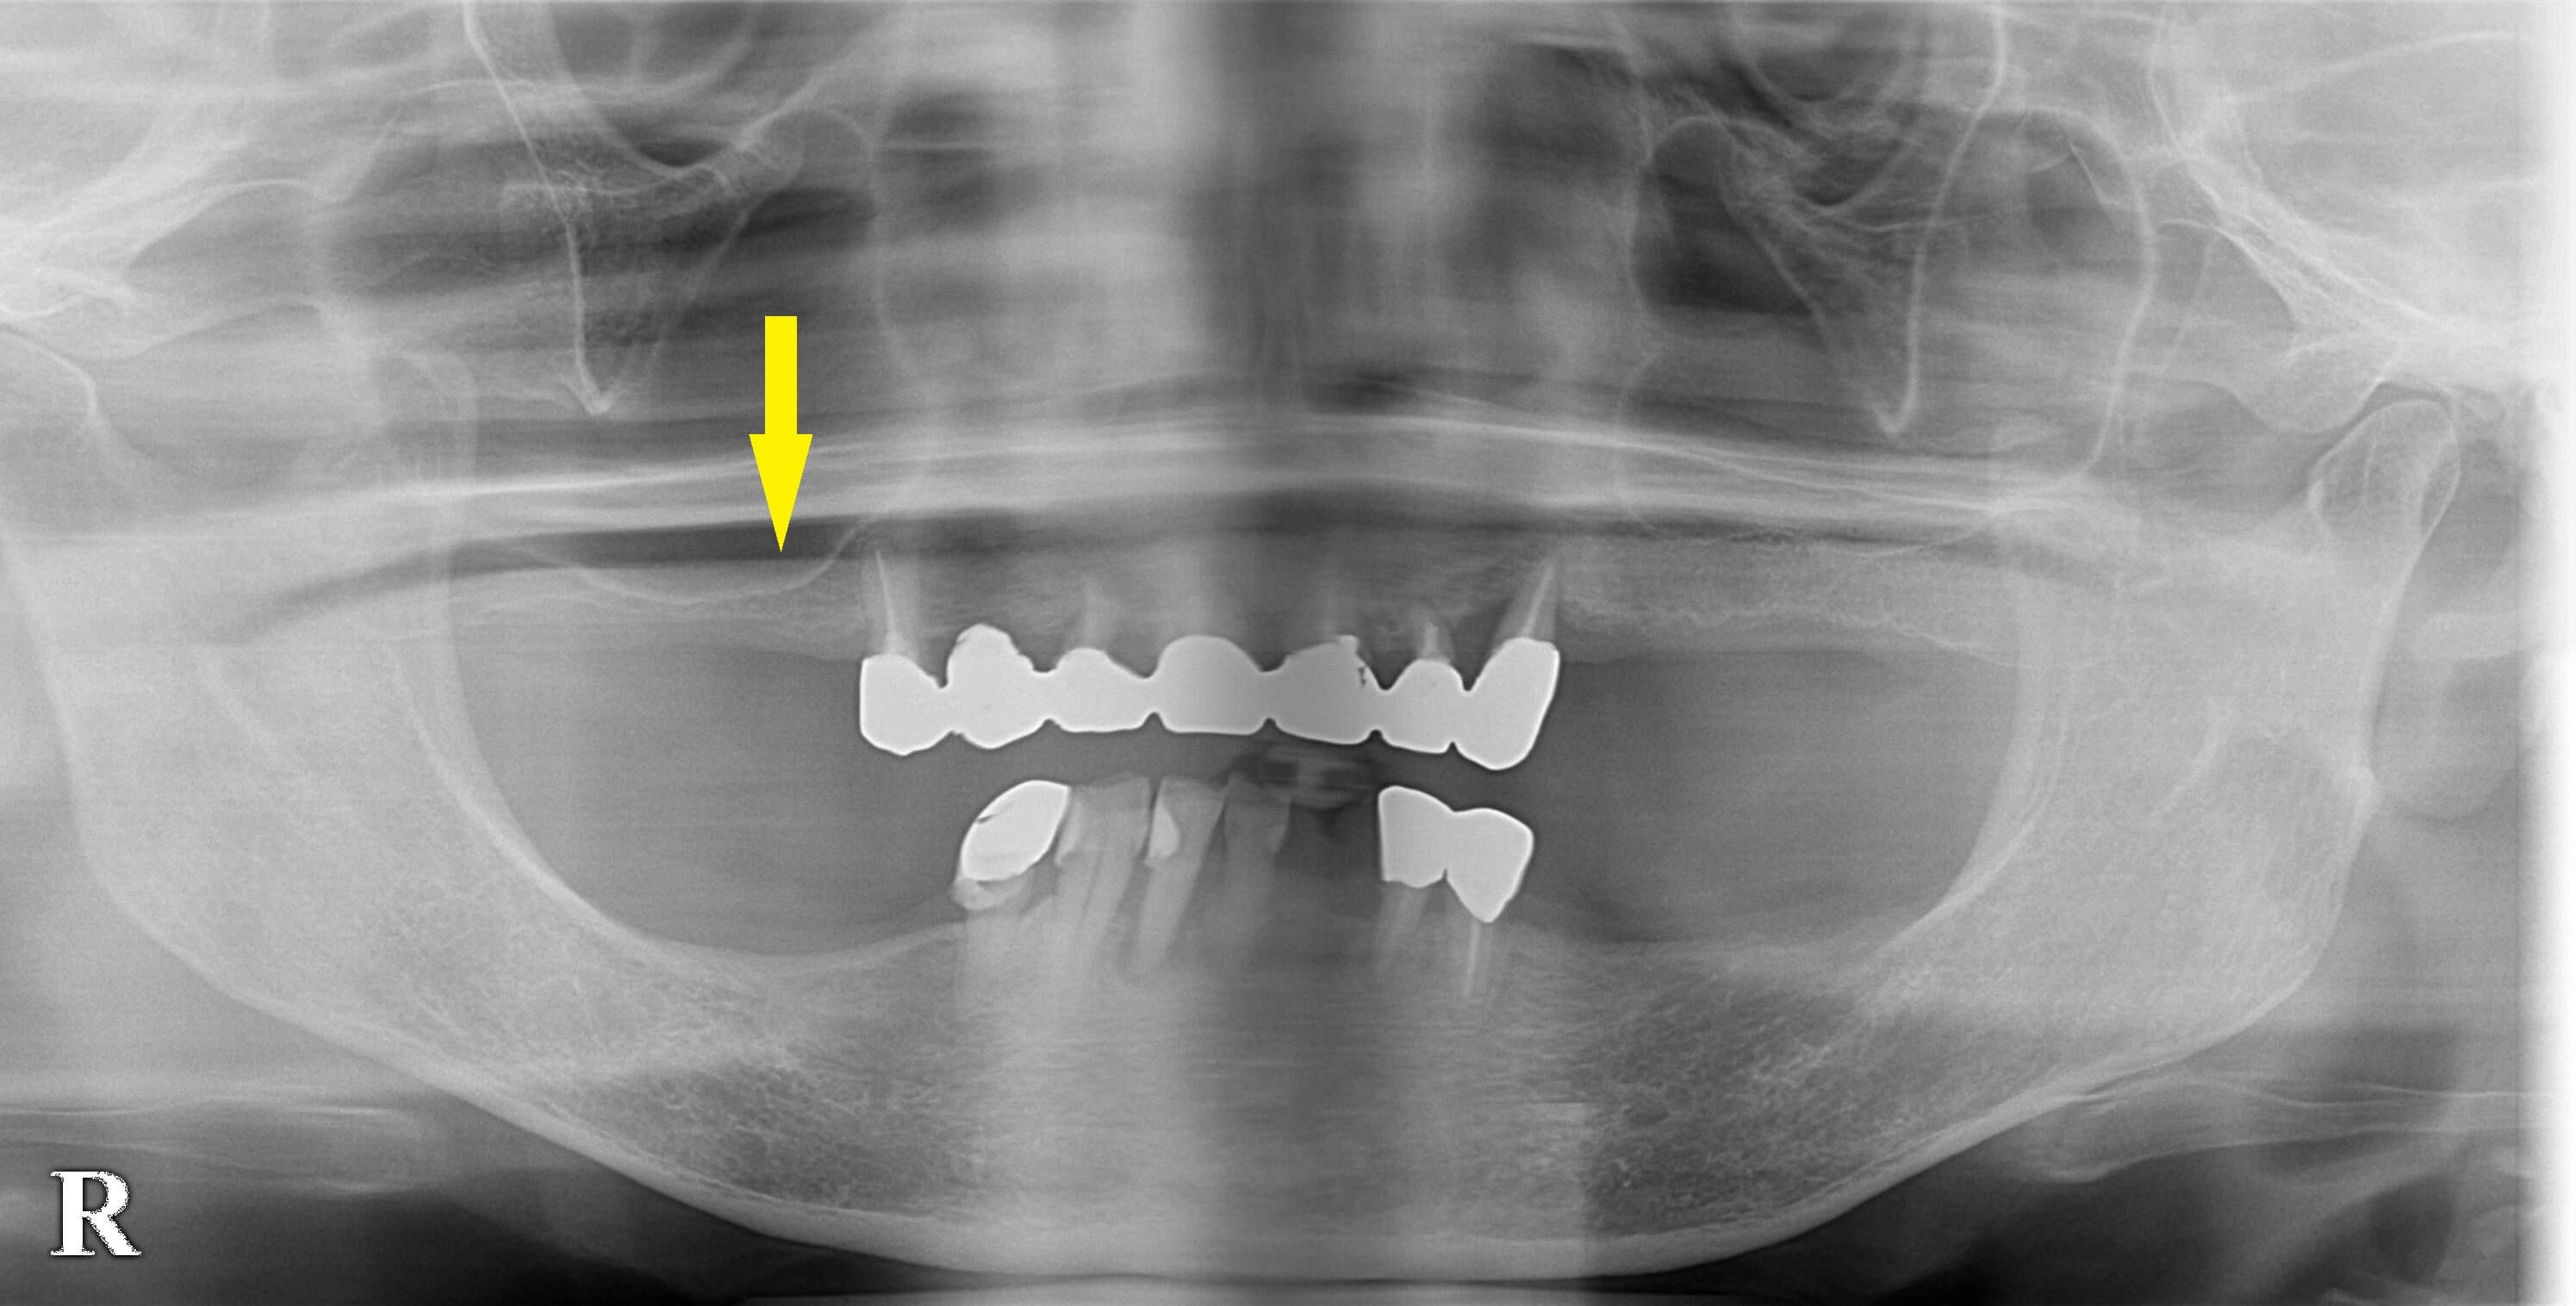

レントゲン写真、CTをみると、どの部位も骨が薄い状態でした。

本日はまず、右上顎に、1本だけ、ソケットリフトという軽めの骨造成を加えてインプラント埋入術を行いました。

今後、順次他の部位の埋入術を行っていく予定です。下に、本日の手術前後のCTを示します。